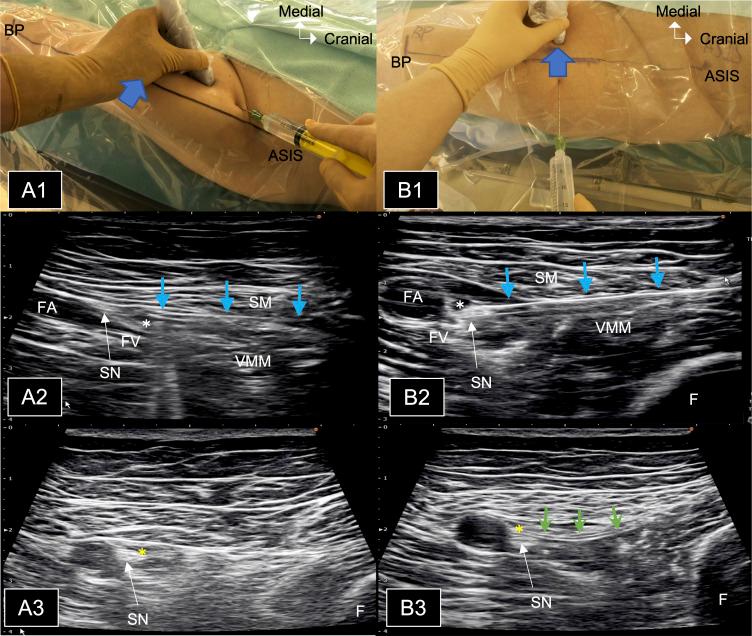

Perineural catheters placed parallel to the nerve course are reported to have lower migration rates than those placed perpendicular to it. However, catheter migration rates for a continuous adductor canal block (ACB) remain unknown. This study compared postoperative migration rates of proximal ACB catheters placed parallel and perpendicular to the saphenous nerve.

Seventy participants scheduled for unilateral primary total knee arthroplasty were randomly assigned for parallel or perpendicular placement of the ACB catheter. The primary outcome was the migration rate of the ACB catheter on postoperative day (POD) 2. Catheter migration was defined as being unable to confirm saline administration via the catheter around the saphenous nerve at the mid-thigh level under ultrasound guidance. Secondary outcomes included active and passive range of motion (ROM) of the knee on postoperative rehabilitation.

与神经走行平行放置的外周神经导管比与之垂直放置的导管迁移率更低。然而,连续收肌管阻滞(ACB)的导管迁移率仍不清楚。本研究比较了平行和垂直于隐神经放置的近端 ACB 导管在术后的迁移率。

70 名计划行单侧初次全膝关节置换术的患者被随机分为平行或垂直放置 ACB 导管。主要结局是术后第 2 天(POD)ACB 导管的迁移率。导管迁移定义为在超声引导下,在大腿中段无法确认导管周围隐神经处的生理盐水给药。次要结局包括术后康复时膝关节的主动和被动活动范围(ROM)。